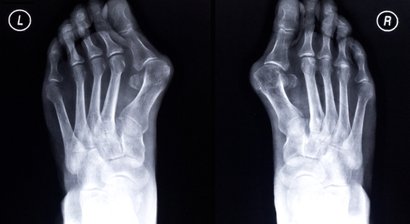

Hallux valgus

Beim Hallux valgus handelt es sich um eine Deformierung des Großzehenballens (Fehlstellung der Großzehe im Grundgelenk nach außen hin), die zumeist mit einer abnormen Spreizung im Bereich vom Mittelfuß einhergeht. Der Hallux valgus ist die häufigste Fehlstellung/Deformit...